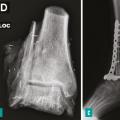

Pour les sarcomes des membres, la préservation de la fonction articulaire est le facteur déterminant. Dans la mesure du possible, les chirurgies avec préservation épiphysaire doivent être privilégiées (fig. 1). En cas d’atteinte épiphysaire, le choix de la technique opératoire dépend de la présence ou non d’un envahissement intra-articulaire, qui nécessite alors de recourir à une résection dite «  extra-articulaire  », techniquement plus exigeante (fig. 2). L’imagerie par résonance magnétique (IRM) a une place de choix pour identifier cette contamination articulaire.

La survenue d’une fracture pathologique rend plus difficile l’obtention de marges saines du fait de la dissémination de l’hématome dans les tissus mous. Elle ne semble pas augmenter le risque de récidive locale – à la condition d’obtenir des marges saines – et ne constitue donc pas une indication d’amputation (fig. 3). Lorsqu’elle survient en cours de traitement, elle fait craindre une mauvaise réponse à la chimiothérapie, qui pourrait expliquer le moins bon pronostic de ces patients.3,4